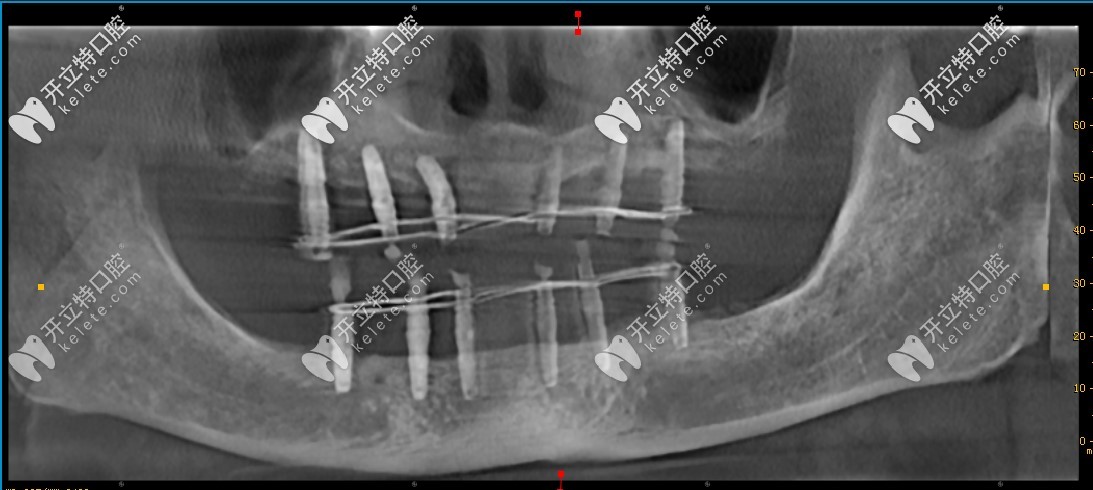

植入種植體后的ct圖

來看效果:從牙片來看,植體已經(jīng)植入牙槽骨內(nèi),接下來只需等待三個月的恢復(fù)期即可,不管是植入的深度或角度,都非常好!